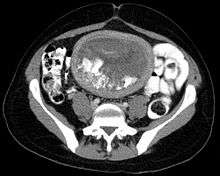

The diagnosis is strongly suggested by ultrasound (sonogram), but definitive diagnosis requires histopathological examination. On ultrasound, the mole resembles a bunch of grapes ("cluster of grapes" or "honeycombed uterus" or "snow-storm"[14]). There is increased trophoblast proliferation and enlarging of the chorionic villi.[15] Angiogenesis in the trophoblasts is impaired as well.[15]